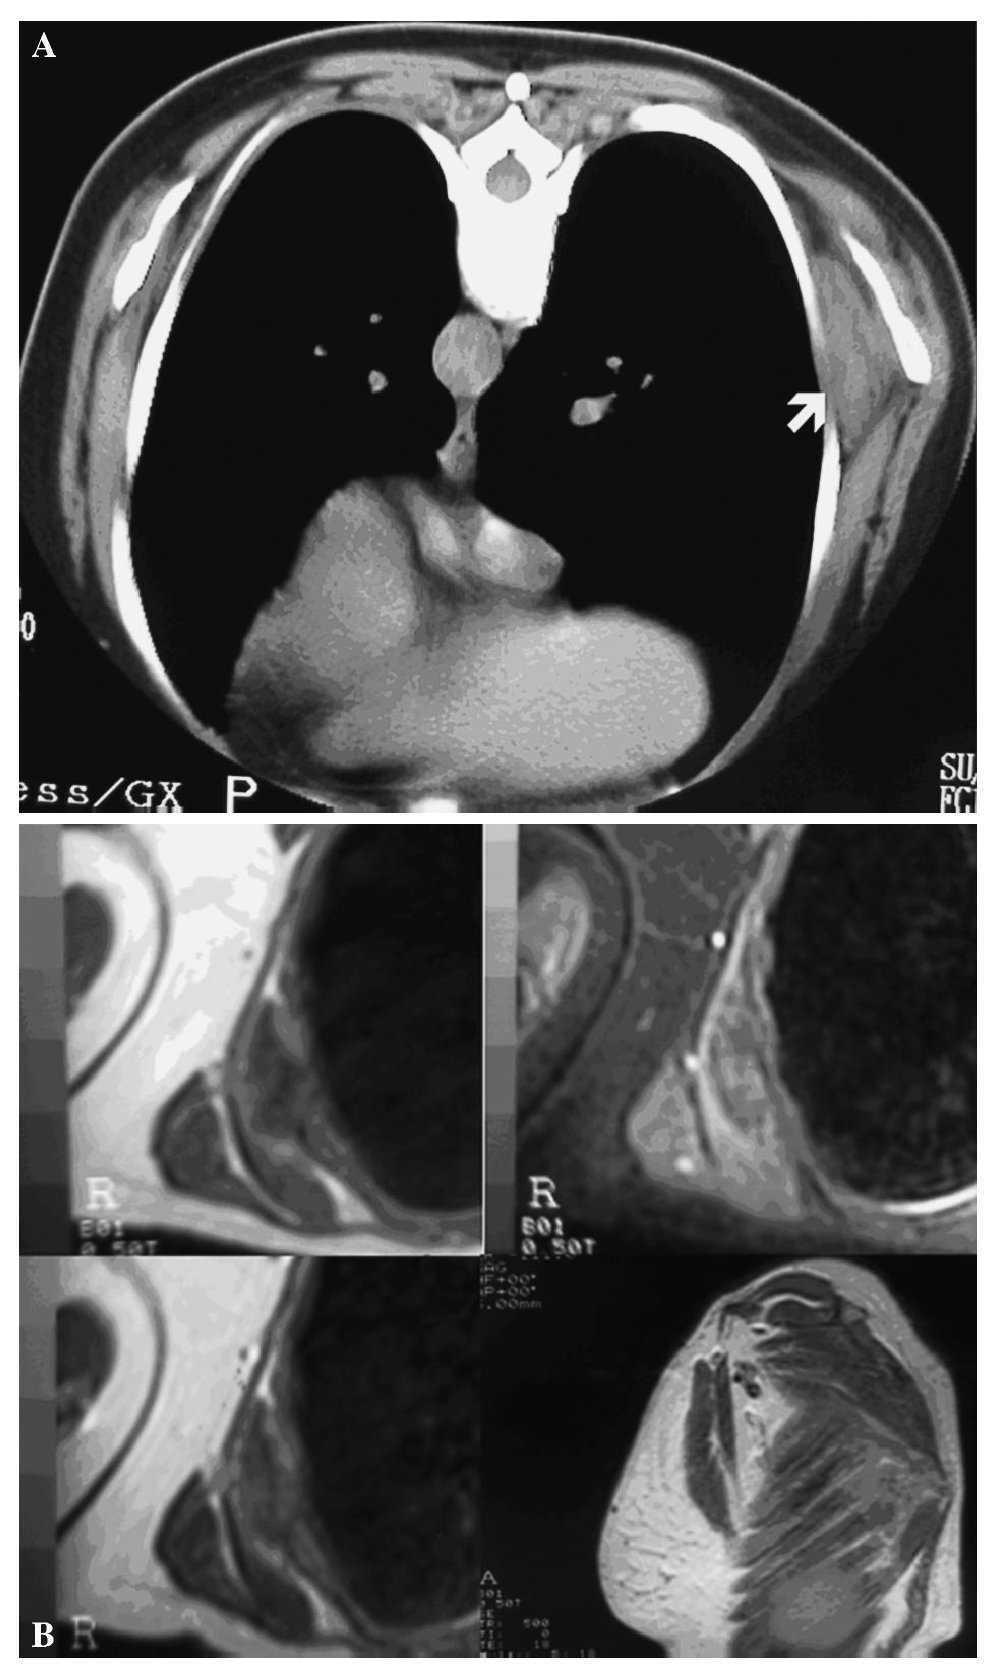

Figura 2.(A) Tomografía computarizada axial sin contraste de la región subescapular de nuestra paciente. Se realiza en decúbito prono a efectos de evitar la compresión de tejidos blandos. Se aprecia una masa de la pared torácica (flecha) de forma lenticular, bien delimitada, no encapsulada, que desplaza anteriormente el músculo serrato mayor y lateralmente el borde inferior de la escápula; presenta una atenuación tisular menor que los músculos y mayor que la grasa subcutánea. Nótense pequeñas áreas lineales de menor densidad dentro de la masa que traduce presencia de grasa. Aunque bien definida por la grasa lateralmente, la lesión no puede separarse de los músculos intercostales. (B) Imágenes de resonancia magnética. a) Secuencia eco de espín potenciada en T1: se aprecia una masa relativamente bien definida con intensidad similar a la del músculo esquelético, con pequeñas áreas curvilíneas mezcladas de alta intensidad; b) en las imágenes potenciadas en T2: masa homogénea, relativamente bien definida, localizada entre la pared torácica y la cintura escapular, que presenta una intensidad parecida al músculo esquelético con áreas lineales entremezcladas de intensidad, que sugiere grasa y que presentan una distribución similar a las imágenes potenciadas en T1; c) y d) incremento heterogéneo de la intensidad tras la administración de gadolinio, como se aprecia en estas imágenes axiales y sagitales potenciadas en T1 en las que se ve un discreto realce, fundamentalmente en la periferia.

El elastofibroma se ubica en hasta en el 99% de los casos en la región subescapular, recibiendo en este caso la denominación de elastofibroma dorsi (figs. 2A y 2B), relacionándose en profundidad con los músculos romboides mayor, latísimo del dorso y serrato anterior, siendo adyacente y medial al ángulo inferior de la escápula. Es bilateral hasta en el 66% de los casos y no es infrecuente la aparición de lesiones sincrónicas en la región infraolecraniana y, más raramente, en la pared torácica y en la tuberosidad isquiática3.